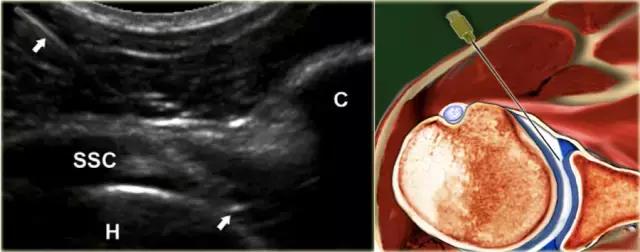

前路途径 在前路方法中,患者仰卧仰卧,伸出的手臂外旋(图)。超声探头在腹侧平行于肩胛腱的长轴放置。探头侧的灰线表示长轴。

使用22号针,针连接到包含造影剂的50mL注射器,由助手保持,在适当的针位置注射15-20mL造影剂时,针垂直于肱骨头的内侧边缘前进,穿透肩胛腱。

如果刺中肱骨头的软骨,针应该拉回1或2毫米,稍微倾斜大约15◦,然后前进切向与头部进入关节,针的斜面朝向关节(图) 。不应该感觉到注射阻力,并且应该看到对比剂自由进入关节并且存在于肩胛下凹部中。

后路方法 A.针处于关节内位置,其中尖端在下筋膜(ISP)和后盂唇(L)下面并且接近肱骨头的透明软骨(星号)。B.相应的尸体标本部分显示最佳针迹(白线)。C. 15毫升注射对比剂后声像图。 针在关节内正确位置可以在注射期间实时可视化,但是也通过由关节内注射的流体在后盂(箭头)的“逗号”样构型来确认。